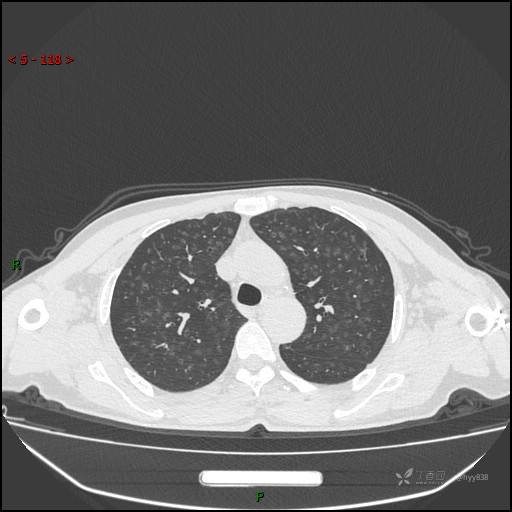

性别:男

年龄:55岁

简要病史:渐进性呼吸困难。

实验室检查:血象正常。

临床诊断:呼吸困难待查

胸部CT平扫

电焊工尘肺 (2)